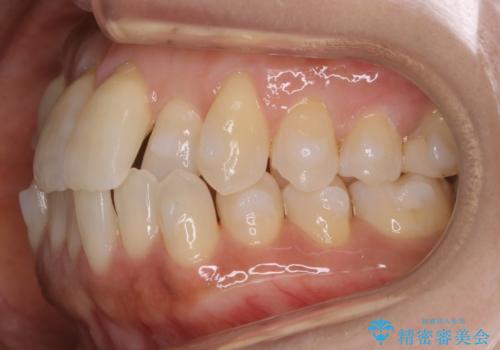

- 前歯のガタつきを主訴に来院されました。

奥歯の噛み合わせにはほとんど問題が見られず、歯列拡大とIPRのみの必要最低限の移動で歯並びの治療を計画することとなりました。